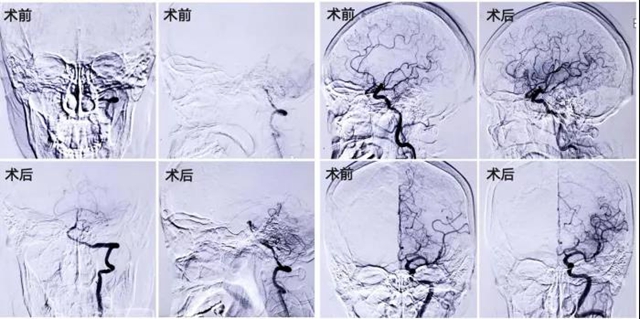

情况紧急,西南医科大学附属中医医院心脑病科副主任兼神经内科副主任刘天助博士接诊后,立即为刘婆婆开通了“脑卒中绿色通道”,紧急会诊,急诊进行头颅CT及术前造影。

结合基层医院CTP检查结果发现,刘婆婆后循环和左侧大脑半球灌注异常,梗死体积小于缺血区域1/3,基底动脉急性、左侧大脑中动脉M2段闭塞rtPA静脉溶栓未能开通,闭塞考虑为心源性栓塞可能。

考虑刘婆婆后循环脑梗死,全麻和右美托咪定镇静后副作用较大,刘天助和家属沟通后决定,在局麻下进行手术,尽量制动刘婆婆头部和肢体。

经过一个小时紧张的手术,刘天助分别从婆婆基底动脉和大脑中动脉取出两块质硬血栓,刘婆婆的脑血管完全恢复了通畅。